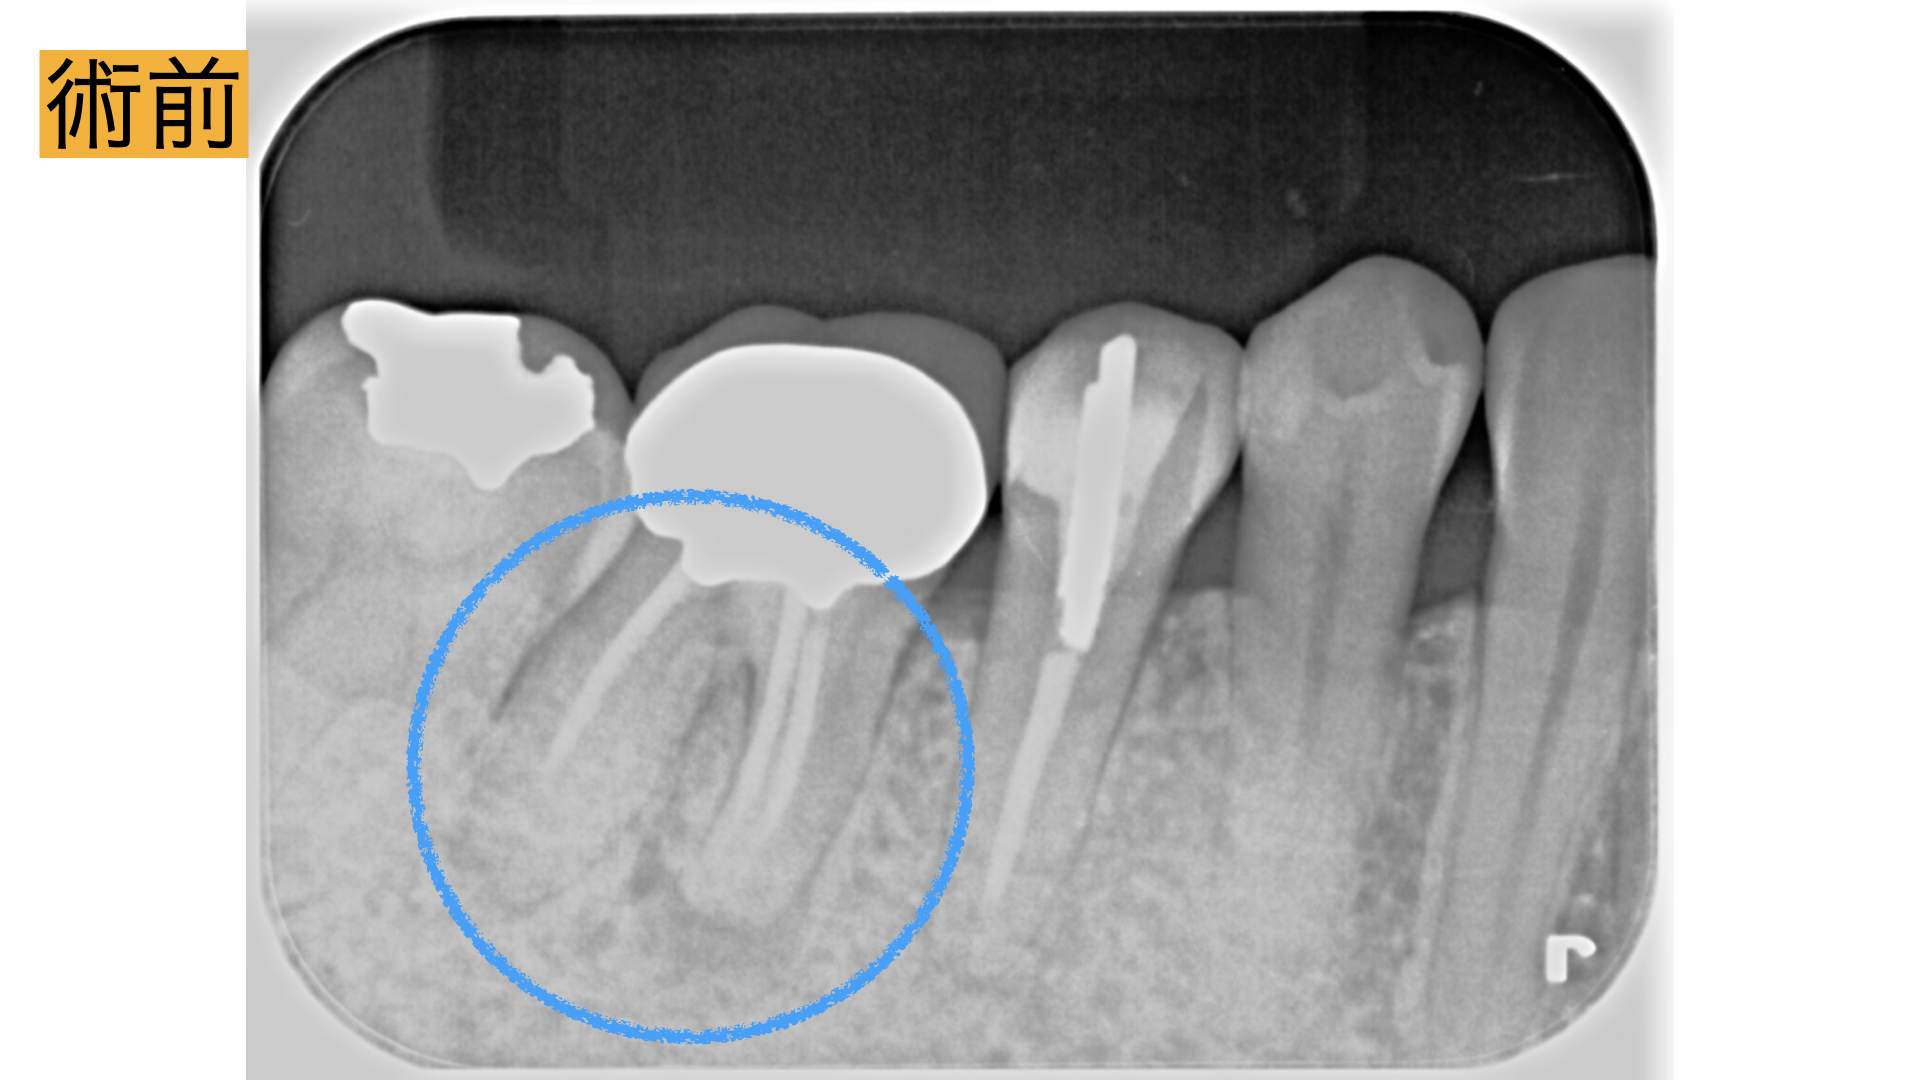

歯茎が腫れた

右下の10年前に治療した歯の歯茎が腫れた、歯磨きすると血が出る。3年前に検診した歯科医院で数年後腫れる可能性があると言われた。日によって歯茎に白いできものができる。できものを潰すと1週間くらい良くなる。 最近、口臭も気になるので治せるのならば治療したい。

カウンセリング

今回、根の治療が3回目とのこともあったため被せ物・土台を外して長期的予後が見込める場合は精密根管治療、見込めない場合は抜歯してブリッジ治療。と決定いたしました。

術後

術直後から痛み、腫れは、解消し2年間の経過観察も問題なく過ごせましたとのことでした。 レントゲンで骨の回復が確認とれ、非常に驚かれておりました。